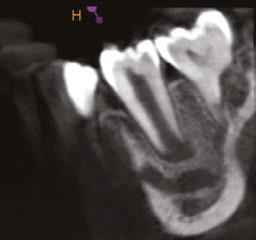

Figure 3 (left): Preoperative CBCT scan of tooth No. 20 showing evidence of a wide open apex. Figure 4 (right): Bleeding noted in the canal immediately after removing the GentleWave platform

In this case report, we present a 10-year-old patient with a wide open apex and a dens evaginatus.5 This case was successfully managed with single visit regenerative endodontics using the GentleWave® System (Sonendo®).6 The outcomes demonstrate not only the feasibility but also the efficacy of this approach in achieving favorable clinical and radiographic results in pediatric patients.

A 10-year-old female patient with a history of swelling and pain associated with tooth No. 20 was referred to our office. The patient exhibited severe dental anxiety. Upon clinical evaluation, a dens evaginatus was noted on the occlusal surface of the tooth (Figure 1). The tooth was sensitive to percussion, palpation, and bite stick while cold testing yielded no response. A periapical radiograph and CBCT scan (Carestream 9600) revealed a wide open apex and evidence of apical periodontitis, leading to the

Figure 1 (left): Dens evaginatus noted on the occlusal surface. Figure 2 (right): Preoperative periapical radiograph of tooth No. 20 showing evidence of apical periodontitis and a wide open apex

diagnosis of a necrotic pulp and symptomatic apical periodontitis of tooth No. 20 (Figures 2 and 3).

Given the presence of a wide open apex, traditional root canal therapy was not possible in this case. Treatment options such as apexification and regenerative endodontics were discussed along with the risks and benefits of both modalities. With apexification, placing the apical plug would present a challenge since there would be a risk of extruding the material past the apex. In addition, this option would present no opportunity for increasing the root width and length. For these reasons, it was determined that pulpal regeneration would be the ideal approach. The goals of the pulpal regeneration procedure would include facilitating root formation while eliminating apical periodontitis and achieving an asymptomatic and functional outcome for the patient. Traditionally, pulpal regeneration would be completed over the course of two visits with interim calcium hydroxide or triple antibiotic paste. However, this 10-year-old patient was severely anxious. Her parents requested for her to be treated under IV sedation. By maintaining the traditional protocol for pulpal regeneration, the patient would have to undergo IV sedation twice at two separate visits.